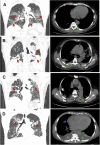

Background: Epidemiological and clinical features of patients with corona virus disease 2019 (COVID-19) were well delineated. However, no researches described the patients complicated with pleural effusion (PE). In the present study, we aimed to clinically characterize the COVID-19 patients complicated with PE and to create a predictive model on the basis of PE and other clinical features to identify COVID-19 patients who may progress to critical condition.

Methods: This retrospective study examined 476 COVID-19 inpatients, involving 153 patients with PE and 323 without PE. The data on patients' past history, clinical features, physical checkup findings, laboratory results and chest computed tomography (CT) findings were collected and analyzed. LASSO regression analysis was employed to identify risk factors associated with the severity of COVID-19.

Results: Laboratory findings showed that patients with PE had higher levels of white blood cells, neutrophils, lactic dehydrogenase, C-reactive protein and D-dimer, and lower levels of lymphocytes, platelets, hemoglobin, partial pressure of oxygen and oxygen saturation. Meanwhile, patients with PE had higher incidence of severe or critical illness and mortality rate, and longer hospital stay time compared to their counterparts without pleural effusion. Moreover, LASSO regression analysis exhibited that pleural effusion, lactic dehydrogenase (LDH), D-dimer and total bilirubin (TBIL) might be risk factors for critical COVID-19.